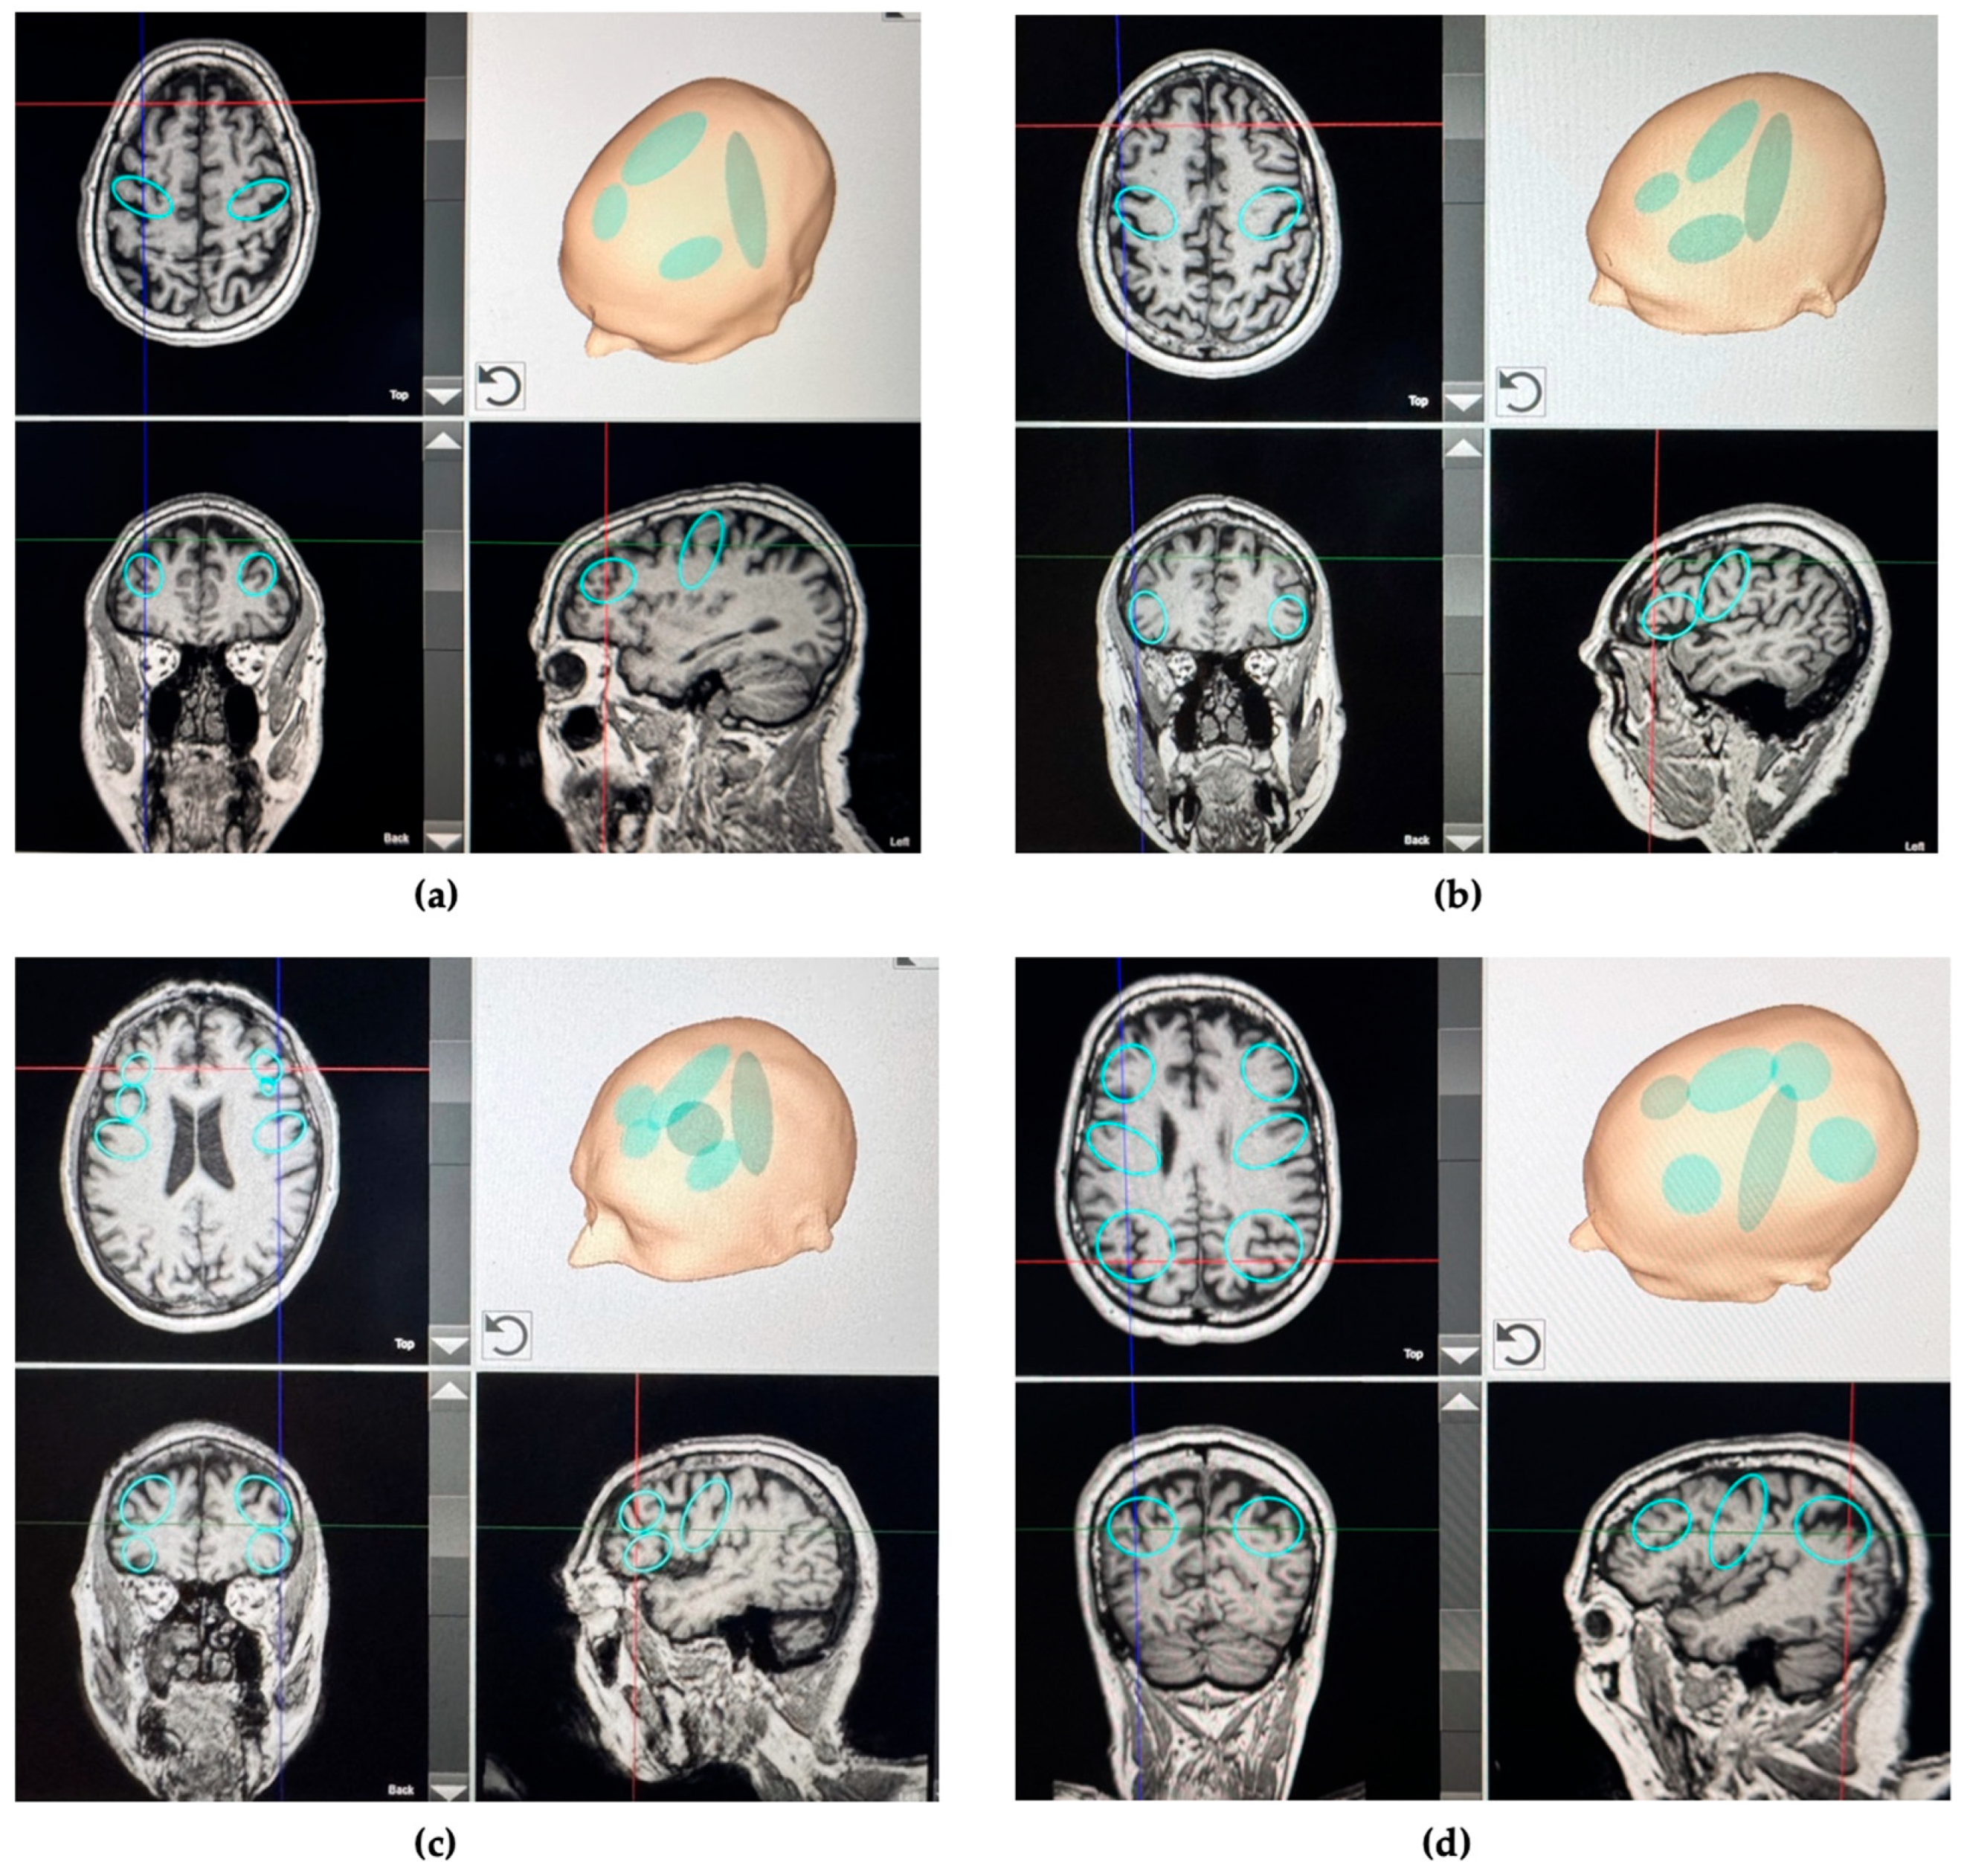

3.2. TPS Protocol

| Symptoms | Clinical Feature | Test Definition | Brain Region of Interest |

|---|---|---|---|

| Motor impairment | Moderate to severe rigidity, freezing of gait, postural instability, tremor, and bradykinesia | UPDRS-III score > 33 | Bilateral and entire strip of the primary motor cortex (M1) |

| Cognitive impairment | Mild memory and executive function alterations | SCOPA-COG ≤ 24 | Bilateral dorsolateral prefrontal cortex (DLPFC) |

| Psychiatric disorder | Depression | BDI-II score ≥ 14 | Bilateral dorsolateral prefrontal cortex (DLPFC) |

| Sleep disorder | Moderate to severe sleep disturbance | PDSS-2 score ≥ 18 | Bilateral posterior parietal cortex (PPC) |

| Fatigue | Moderate to severe fatigue | PFS-16 binary score of >8 | Bilateral dorsolateral prefrontal cortex (DLPFC) |

| Voice/speech dysfunction | Moderate to severe dysarthria and poor voice control | VHI-10 score ≥ 11 | Bilateral inferior frontal cortex extending on the left to Broca’s area |

| Taste and smell disorders | Moderate or severe olfactory and gustatory dysfunction | VAS for taste or smell ≥ 4 | Bilateral orbitofrontal |